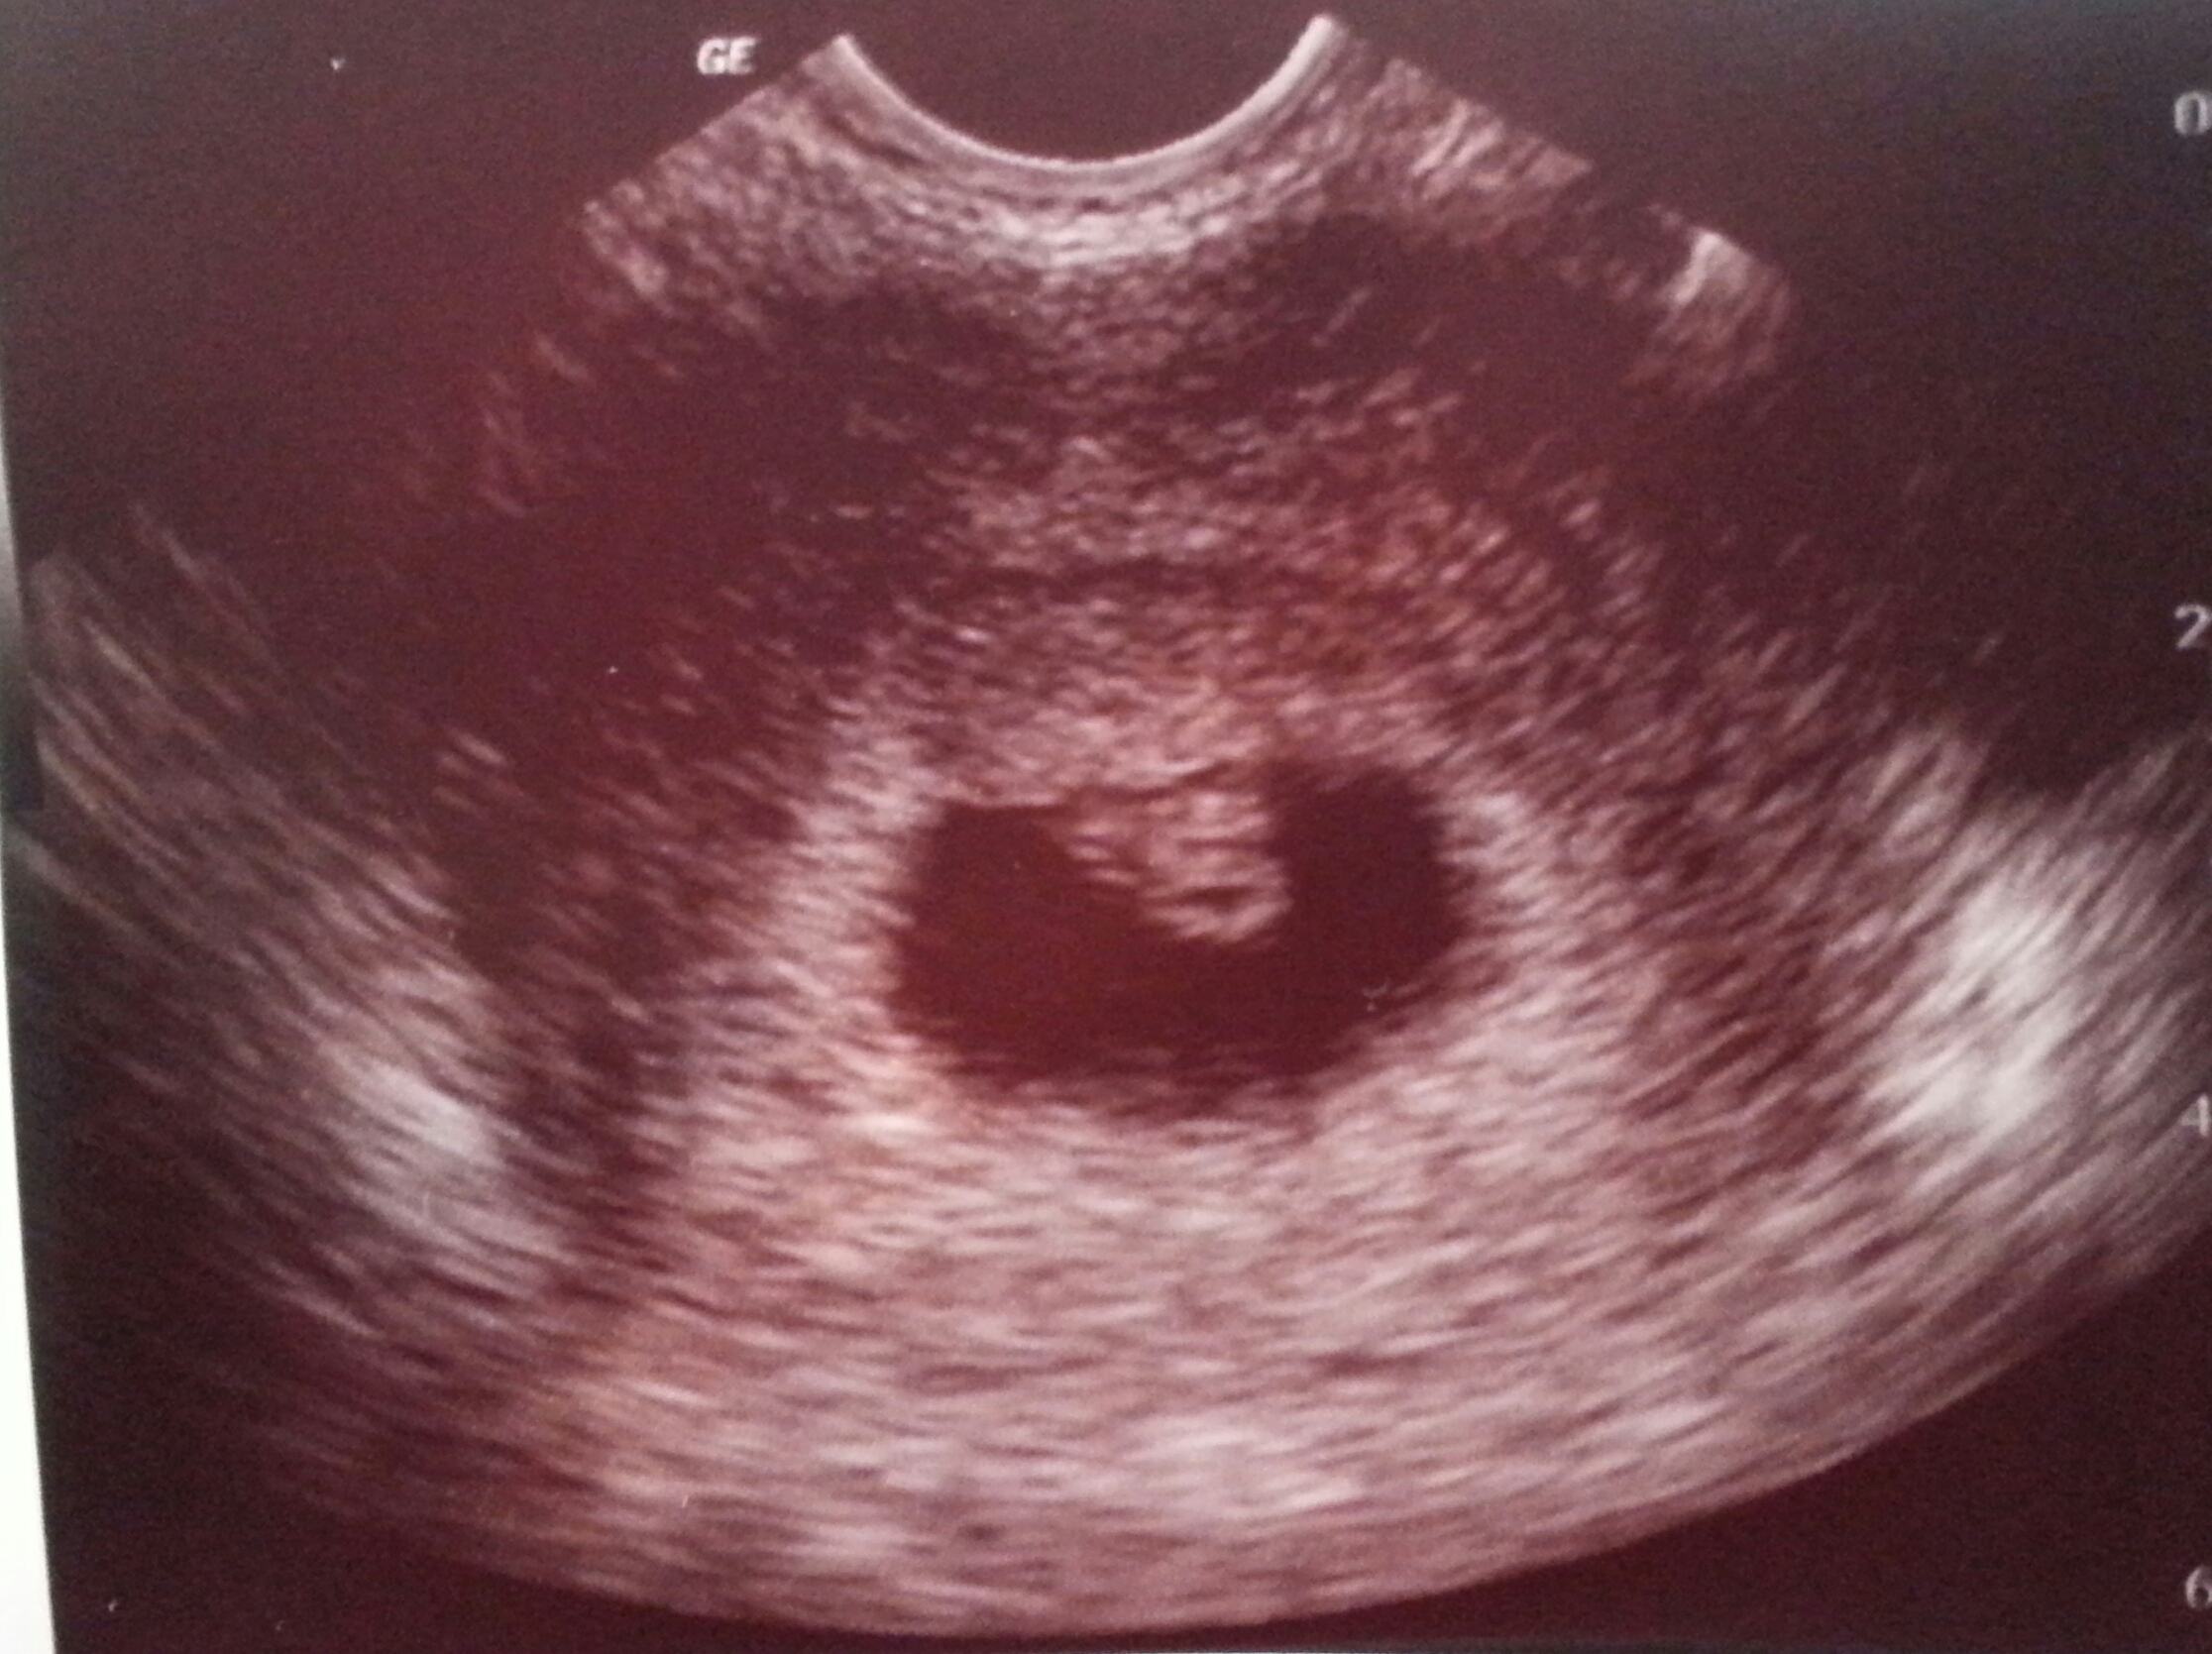

I know it is still early but some of you have already had your first ultrasound.

Feel free to share your picture(s) as you have them done!

Also be sure to include any information related to the U/S that you want to share with the group (how many weeks, heart rate, type of U/S, etc.).

Thought i was further along.. Had a early scan because i had an mc 2 months ago.

Next week follow up to see if she/he has grown. Nervous!